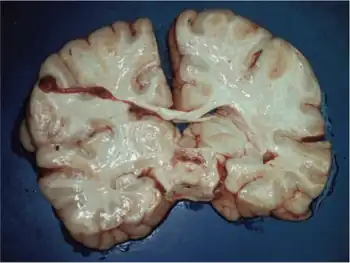

The characteristic symptoms of Leigh syndrome are at least partially caused by bilateral, focal lesions in the brainstem, basal ganglia, cerebellum, and other regions of the brain. The lesions take on different forms, including areas of demyelination, spongiosis, gliosis, necrosis, and capillary proliferation.[7]

Demyelination is the loss of the myelin sheath around the axons of neurons, inhibiting their ability to communicate with other neurons. The brain stem is involved in maintaining basic life functions such as breathing, swallowing, and circulation; the basal ganglia and cerebellum control movement and balance. Damage to these areas therefore results in the major symptoms of Leigh syndrome—loss of control over functions controlled by these areas.[1]